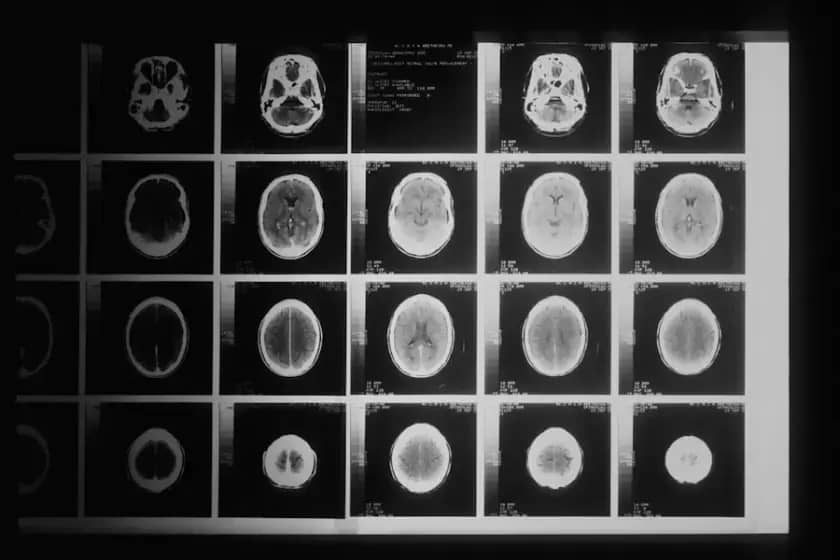

Svi ponekad zaborave telefon ili imaju glavobolje. Ipak, ponekad svakodnevni problemi mogu biti rani znaci tumora na mozgu. Studija naučnika sa Univerziteta Kvin Meri u Londonu otkrila je da pacijenti i lekari često ignorišu rane simptome, što može odložiti dijagnozu tumora na mozgu. Rani znaci tumora na mozgu često se preklapaju sa stresom, umorom, migrenama ili anksioznošću.